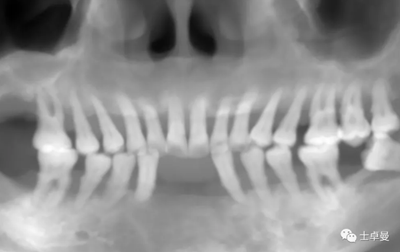

影像學檢查

CBCT檢查:顯示口內(nèi)余留牙牙槽骨吸收至根尖1/3;

上頜雙側后牙區(qū)上頜竇底可用骨高度不足;

下頜雙側后牙區(qū)下頜神經(jīng)管上方可用骨高度不足。